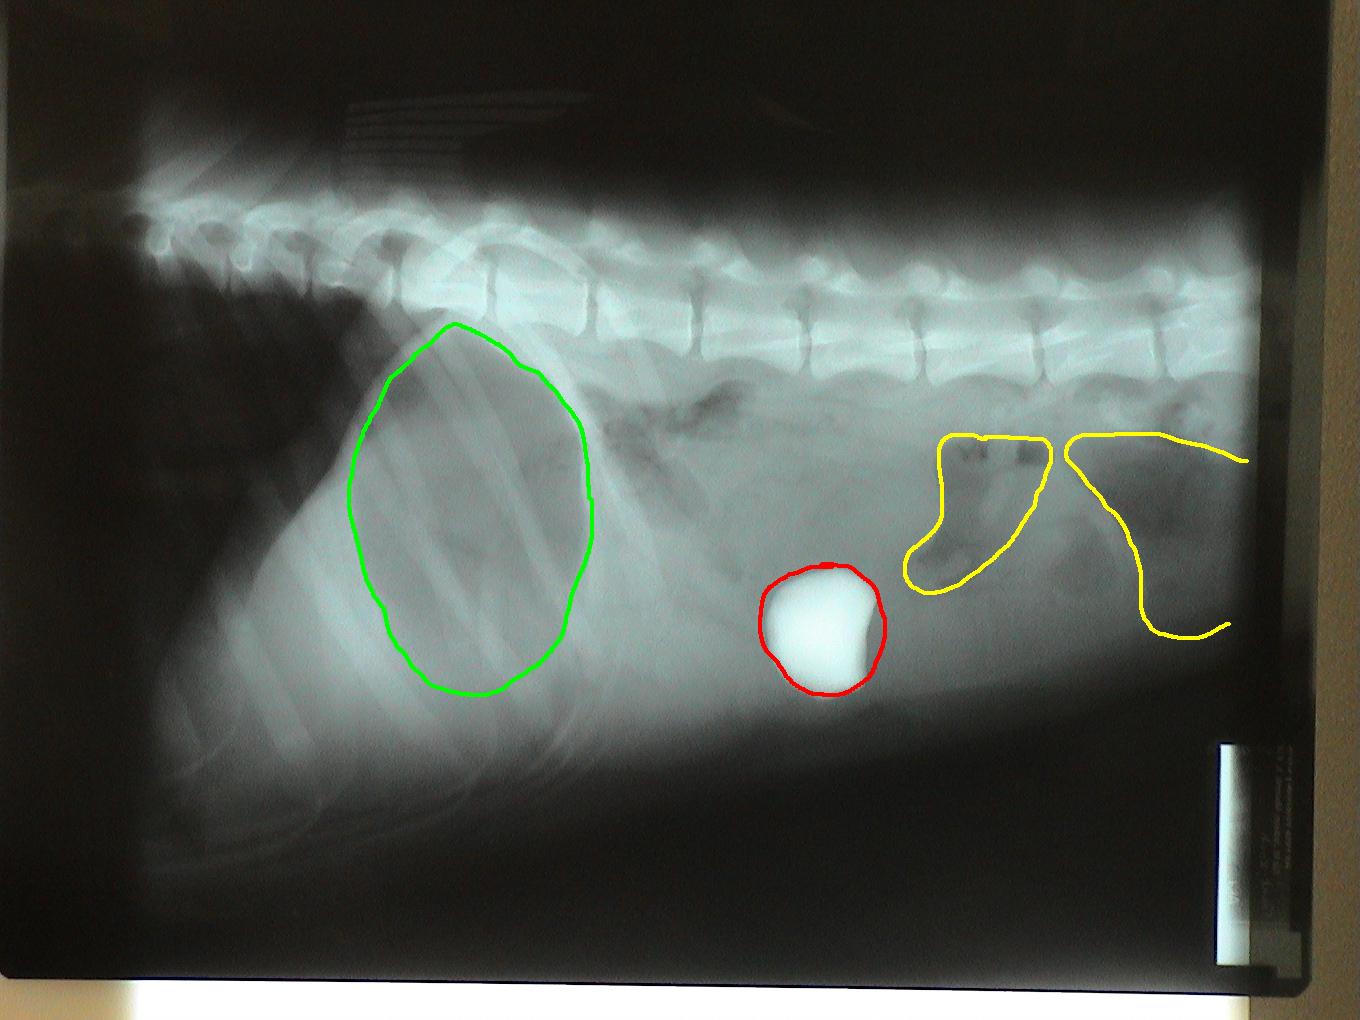

Radiographs (x-rays) were taken and his problem became very obvious! A previously ingested rock had become lodged in the small intestine causing an obstruction.

Green circle: Gas filled stomach. Secondary to vomiting, the stomach can become distended with gas. Red circle: Rock in small intestine. Yellow circle: Gas in colon. Secondary to an obstruction, gas can accumulate in the bowel.

Two sets of radiographs are always taken to localize lesions and identify problems. Radiographs are flat pictures of three-dimensional animals! If one view is taken, things can be lost as structures will overlap each other. For example, the rock is located on the left side of the abdomen which is clearly evident on the second set of radiographs. This is not evident in the first set since the left and right sides of the dog overlap each other.

Notice the difference in the shape of the circled structures depending on the position of the animal.